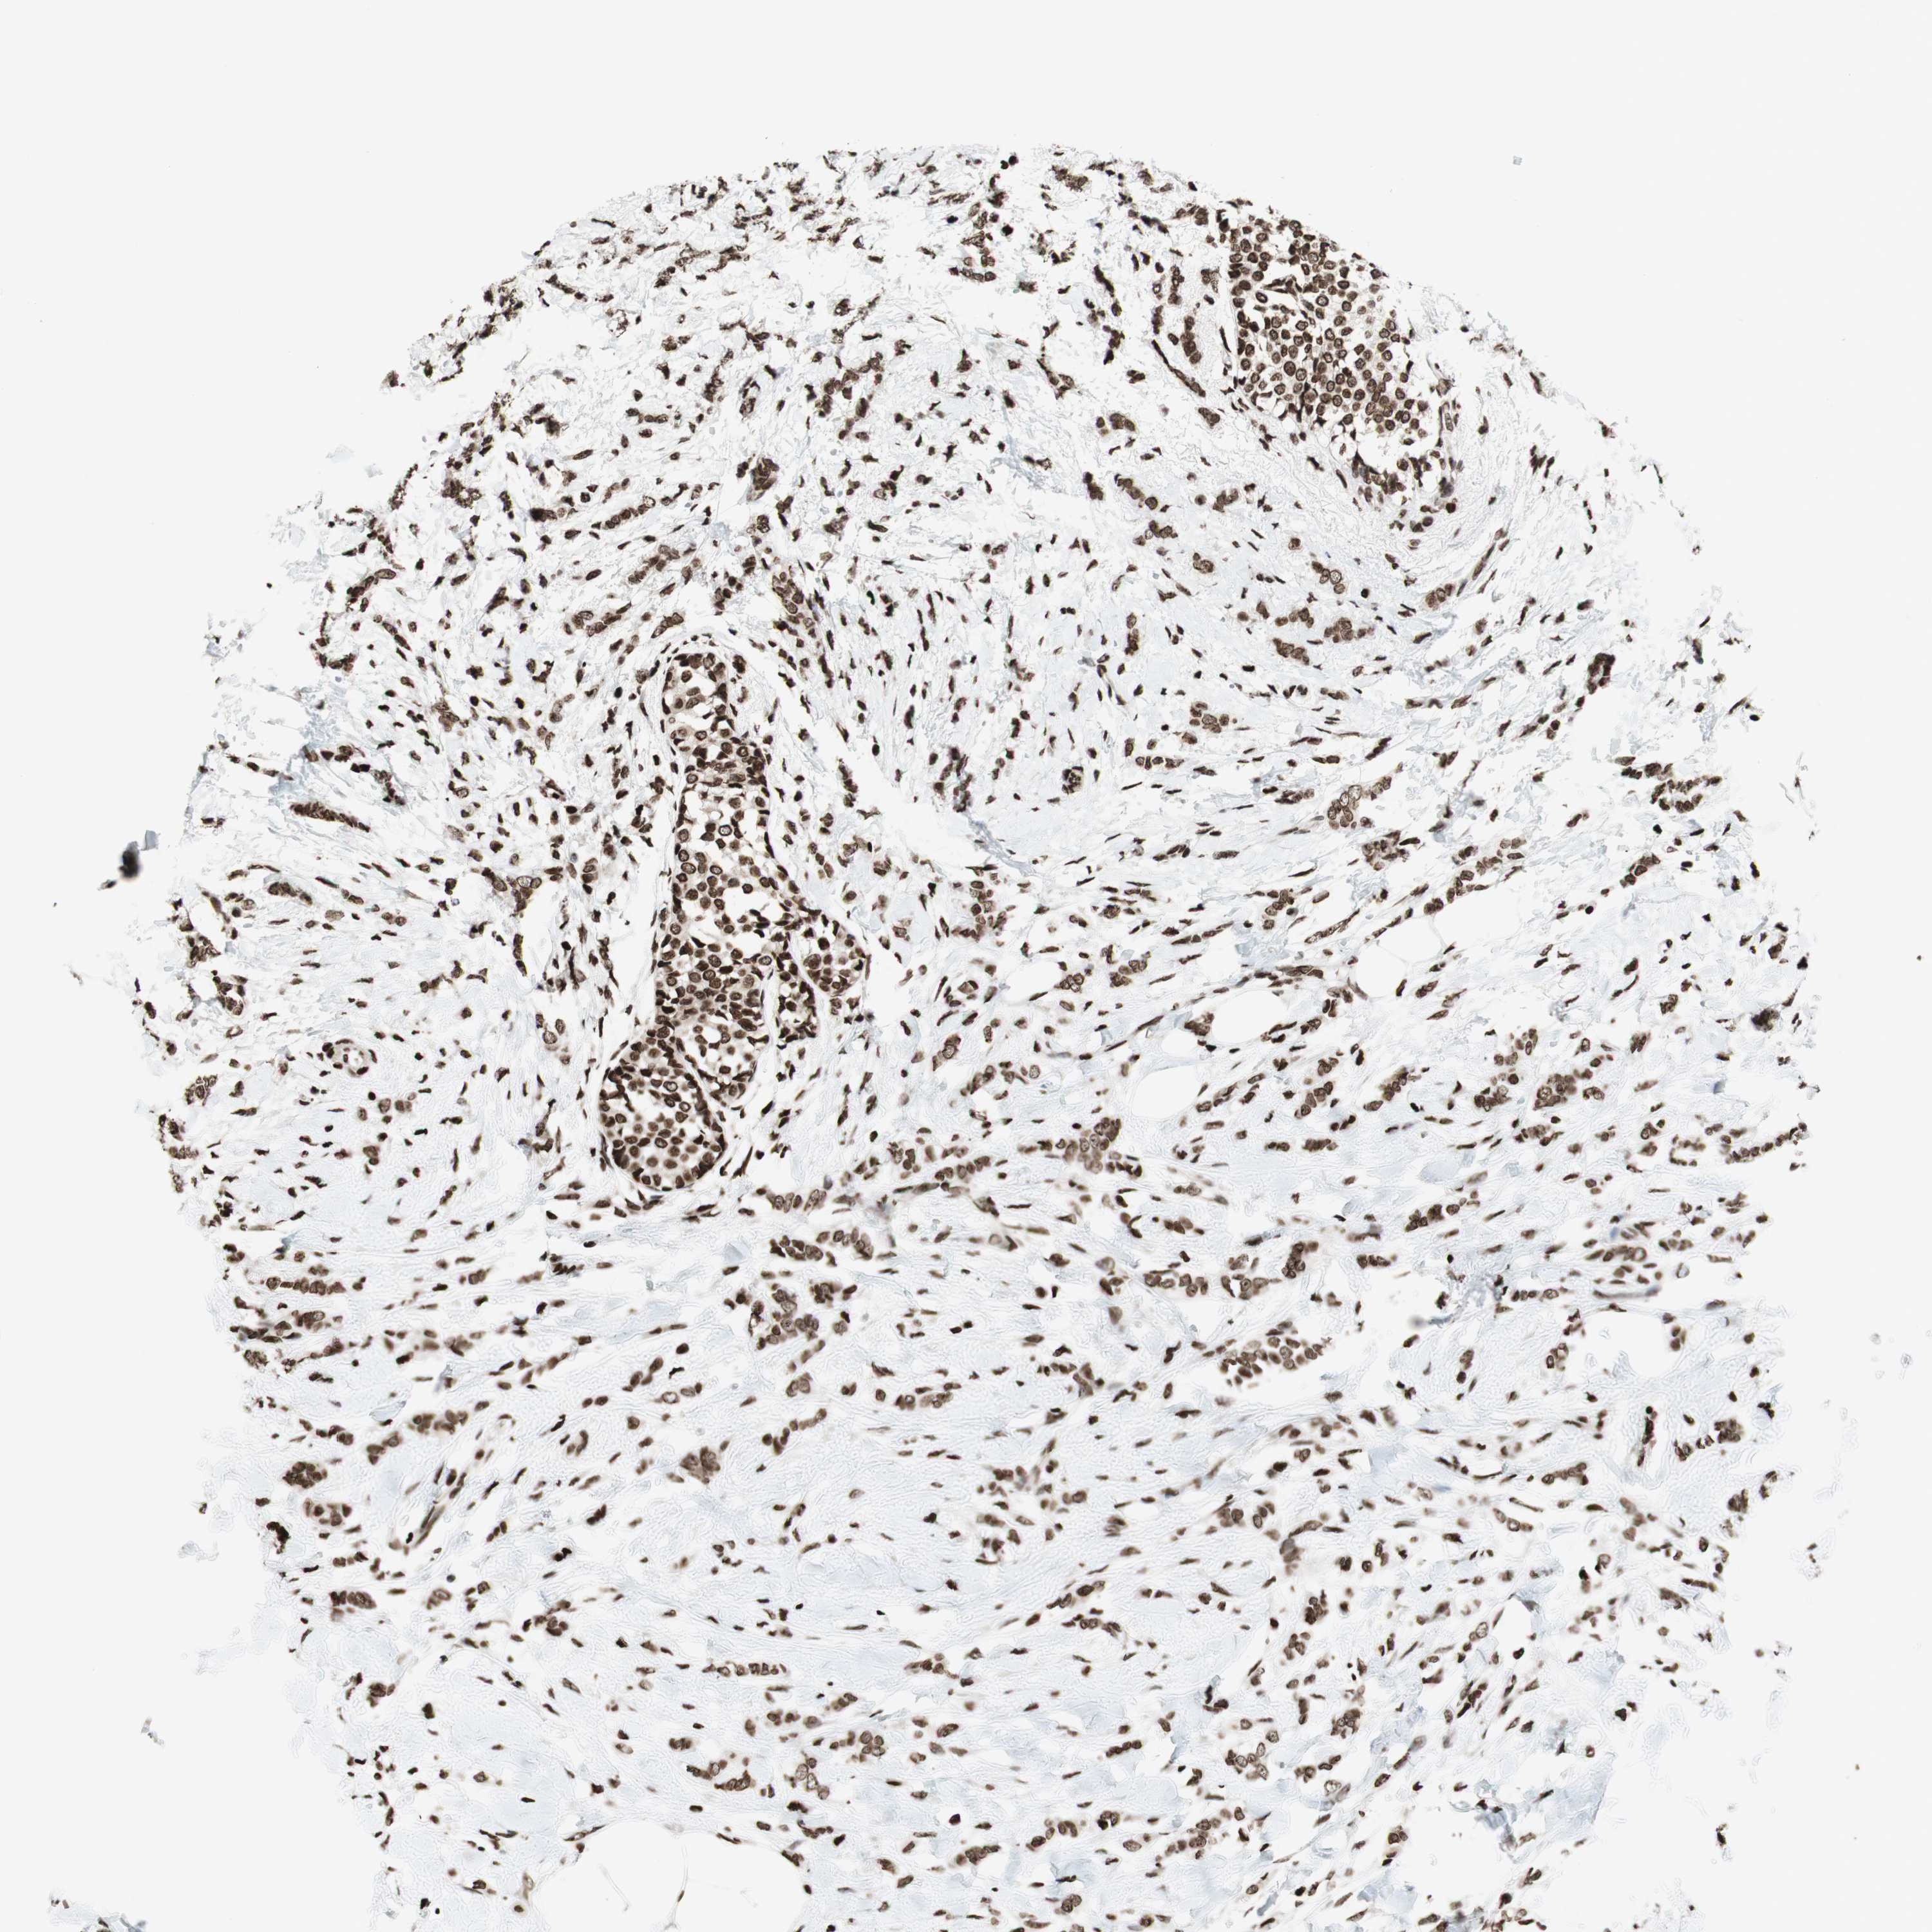

BRCA TCGA BRCA VALIDATION PROTEIN EXPRESSION

ANTIBODIES

AND

VALIDATION